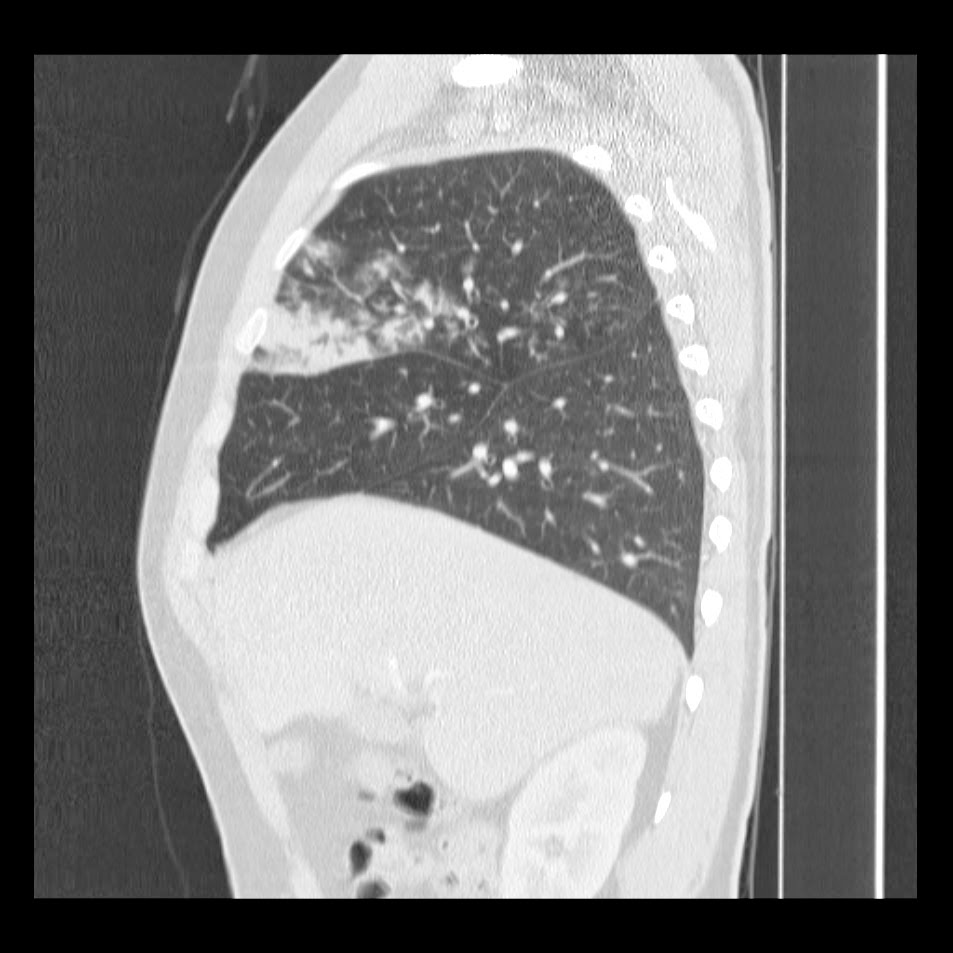

Respuesta al Caso #6

Segmento lateral del lóbulo medio